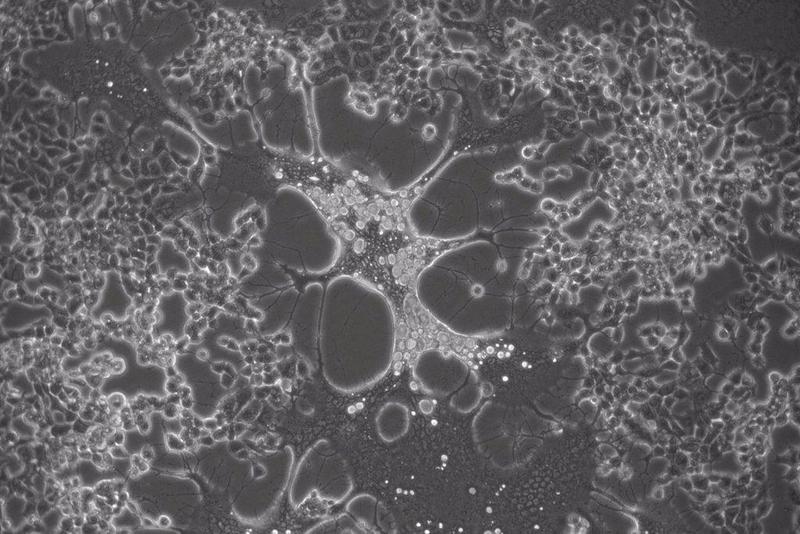

Un estudio del Consejo Superior de Investigaciones Científicas (CSIC) ha mostrado, por primera vez, que los virus humanos herpes simplex mutan in vitro más rápido de lo que se pensaba. Los resultados del trabajo, publicado en la revista 'PLOS Pathogens', indican además que el virus herpes simplex tipo 2, causante del herpes genital, es capaz de evolucionar más rápido que su homólogo labial, el virus herpes simplex tipo 1, en cultivo celular.

"El virus del herpes simple es uno de los patógenos humanos más prevalentes a nivel mundial, para el cual no existe cura o vacuna. Tradicionalmente se pensaba que estos virus de ADN evolucionaban muy lentamente, comparado con sus parientes de ARN, que lo hacen a una velocidad muy elevada. Hemos encontrado que ambos tipos de herpes simplex, el tipo 1 o herpes labial y el tipo 2 o herpes genital, acumulan cambios cuando replican en cultivo celular, lo que puede incluso hacer cambiar su fenotipo muy rápidamente", explica el investigador Antonio Alcamí, del Centro de Biología Molecular Severo Ochoa (CBM-CSIC-UAM), centro mixto del CSIC y la Universidad Autónoma de Madrid.

"Estos virus humanos han sido propagados en cultivo celular durante décadas en laboratorios de todo el mundo. El impacto que estas técnicas de cultivo in vitro puedan tener en la generación de diversidad genética de estos virus no había sido caracterizado hasta ahora. Hemos optimizado un método que permite detectar mutaciones nuevas que aparecen con muy baja frecuencia en la población viral cuando estos virus replican. Gracias a ello, hemos sido capaces de observar cómo el virus del herpes simplex tipo 2 genera, de forma consistente, muchas más mutaciones al replicar que su homólogo labial (tipo 1), lo que se traduce en una tasa evolutiva más rápida para el primero", concluye el investigador Alberto Domingo López Muñoz, del Instituto Americano de Alergias y Enfermedades Infecciosas.